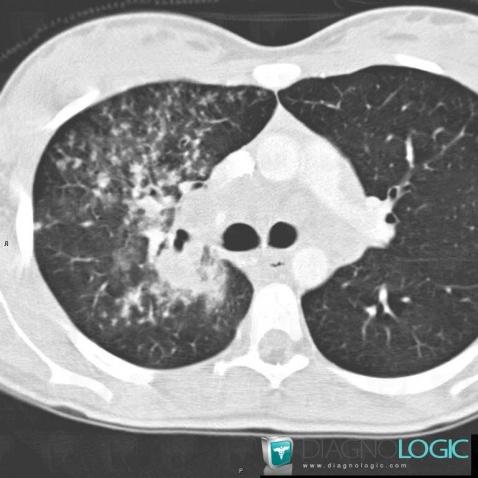

Voici les informations spécifiques à l'image clé ci dessus:

- Diagnostic Tuberculose , Localisation(s) Parenchyme pulmonaire, comportant les gammes Micronodules centrolobulaires pulmonaires

Voici les informations spécifiques à l'image clé ci dessus:

- Diagnostic Tuberculose , Localisation(s) Parenchyme pulmonaire, comportant les gammes Micronodules centrolobulaires pulmonaires